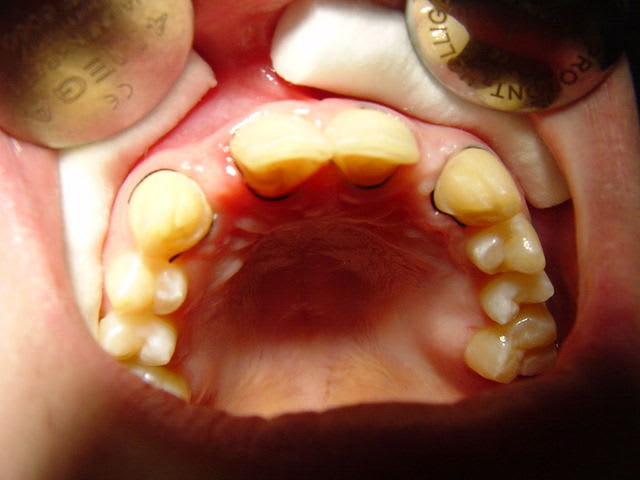

ceci par exemple

Dsc00090 mq4djg - Eugenol

Dsc00089 nurt6y - Eugenol

préparations pour bridge collé ...des commentaires?